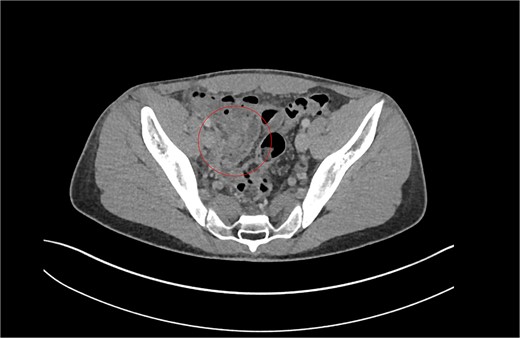

Review of previous notes revealed that the patient had a laparoscopic appendicectomy 2 years prior from a CT-confirmed acute retrocaecal appendicitis with localized perforation at the tip (Fig. 1). Intraoperatively, the dissection proved difficult due to the presence on multiple inflammatory adhesions and the retrocaecal position of the appendix, however a retrograde appendicectomy was completed laparoscopically. The postoperative period was complicated by a right iliac fossa abscess that was successfully treated with IV antibiotics and CT-guided drainage. The index histology revealed multiple pieces of appendiceal tissue aggregating to 60 mm × 40 mm × 20 mm, with acute inflammation and necrosis.

Patient A. Appendiceal stump of Patient A identified within the red circle on CT scan before the second operation.